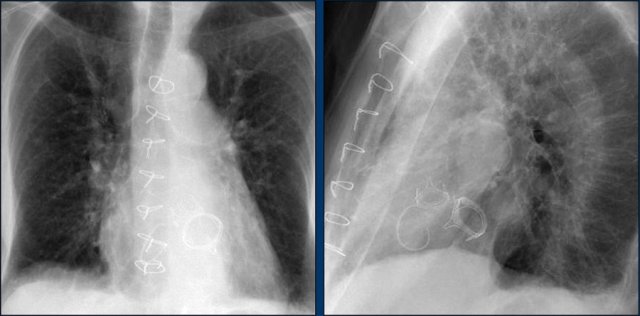

This patient has three valves repaired:

• Mitral

• Tricuspid

• Aortic

There is a pacemaker with epicardial leads.

This was done, because it was thought that a normally placed lead to the right ventricle would interfere too much with the function of the tricuspid valve prosthesis.

White arrow points to aortic valve.

Yellow arrow points to mitral valve.